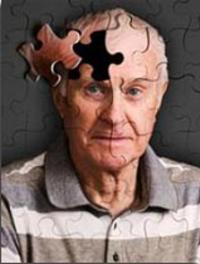

L’association insuffisance cardiaque gauche et sibilants définit « l’asthme cardiaque » ou le « pseudo-asthme cardiaque ». Il représente jusqu’à un tiers des formes cliniques des patients âgés. Si la constatation clinique est classique, les mécanismes physiopathologiques impliqués dans ce phénomène sont plus complexes. Les comorbidités respiratoires et l’impact favorable des traitements bronchodilatateurs participent à la confusion. Les cliniciens décrivent lors de poussées [...]